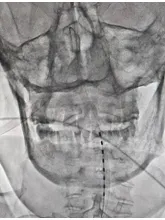

▲ 短时程脊髓电刺激电极置入术,正侧位透视片

经传统促醒手术:颅骨修补手术、脑积水分流手术,再次复查脑功能磁共振、昏迷脑电图评估后,昏迷评分较前提高。经科室讨论,神经外科一病区寿记新主任总结指出:该患者可先行短时程脊髓电刺激手术治疗,若治疗效果明确,可行二期电极及刺激器永久植入。2024年11月13日,小王完成了短时程脊髓神经刺激测试电极置入手术。